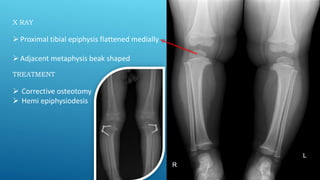

X RAY

Proximal tibial epiphysis flattened medially

Adjacent metaphysis beak shaped

TREATMENT

 Corrective osteotomy

 Hemi epiphysiodesis